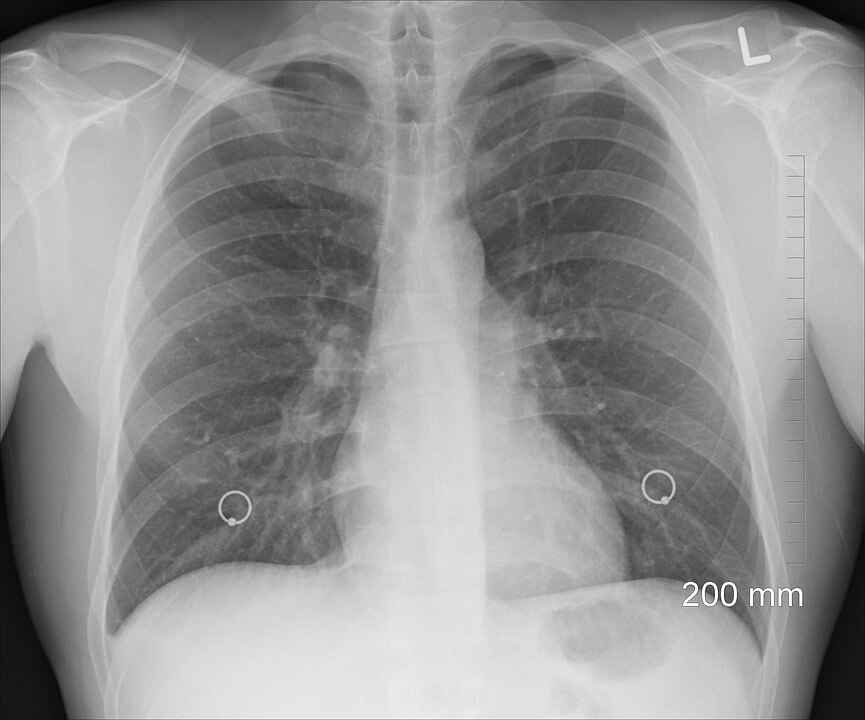

Stay up to date with the latest information, news, services and events by signing up to our database. Lung cancer is the fifth most common cancer in australia and accounts for 9% of all cancers. Or to the fluid around the lungs or heart (malignant effusion); Symptoms of this disease may be referred to as pancoast syndrome and include pain in the shoulder, inner side of the arm, and hand. Lung cancer is the leading cause of cancer death in australia.

Lung Cancer In Australia Statistics Cancer Australia from www.canceraustralia.gov.au Lung cancer usually has no symptoms in its early stages. In our 14th episode of understanding, managing, living with lung cancer series we discuss the symptoms associated with lung cancer. Or to the lining around the lungs or the heart; Or to the fluid around the lungs or heart (malignant effusion); In australia, lung cancer is the fifth most common cancer. Lung cancer is the leading cause of cancer deaths worldwide. Each year, about 12,200 australians are diagnosed with lung cancer. A person diagnosed with lung cancer may also have symptoms such as fatigue, weight loss, hoarse voice, wheezing, difficulty swallowing, abdominal or joint pain, and enlarged fingertips (finger clubbing).

1 from When signs of the disease start to appear, they can include: In quantitative findings, haemoptysis and dyspnoea were the most recognised symptoms across the sample population. Or to the lining around the lungs or the heart; The risk of being diagnosed with lung cancer in australia by age 90 is 1 in 18. It is the fifth most common cancer in australia, accounting for 9% of all cancers diagnosed. If it spreads you might develop other symptoms like nausea, headaches and pain in other parts of your body. Lung cancer is the leading cause of cancer death in australia. It is the leading cause of death due to cancer.